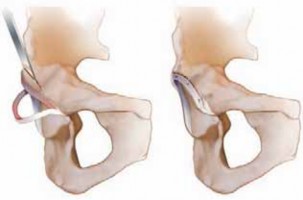

28. A Z-shaped capsulotomy for the right hip and an inverse Z-shaped capsulotomy for the left hip are performed (

TECH FIG 3B

), taking care not to injure labrum and cartilage.

1. The longitudinal limb of the capsulotomy is performed parallel to the axis of the femoral neck, starting at the anterosuperior edge of the stable trochanter. Medially, the capsulotomy is in line with the anterior intertrochanteric line, leaving a cuff of capsular tissue for later reattachment, and extends down toward the lesser trochanter, but stops anterior to it to avoid injury to the MFCA, which runs posterosuperior to the lesser trochanter.

2. The proximal transverse limb of the incision is performed by incising the capsule along the superior acetabular rim until the piriform muscle is reached.

1. These steps keep the limb away from the capsular perforation of the MFCA.

29. The femoral head is dislocated anteriorly to allow inspection of the acetabulum.

1. Flexion and external rotation are used to place the leg in the sterile side bag (

TECH FIG 3C,D

).

2. With traction on a bone hook around the calcar, the femoral head is dislocated, and curved scissors are used to cut the ligamentum capitis femoris.

3. External rotation aids in opening up the anterior joint space and tensioning the ligament for easier trans-section.

30. Lowering the knee lets the femoral head rise automatically out of the surgical site, allowing its full inspection.

1. Two blunt Hohmann retractors are placed around the neck (

TECH FIG 3E

31. To view the acetabulum, the knee is brought higher than the pelvis, and a gentle axial push allows the head to